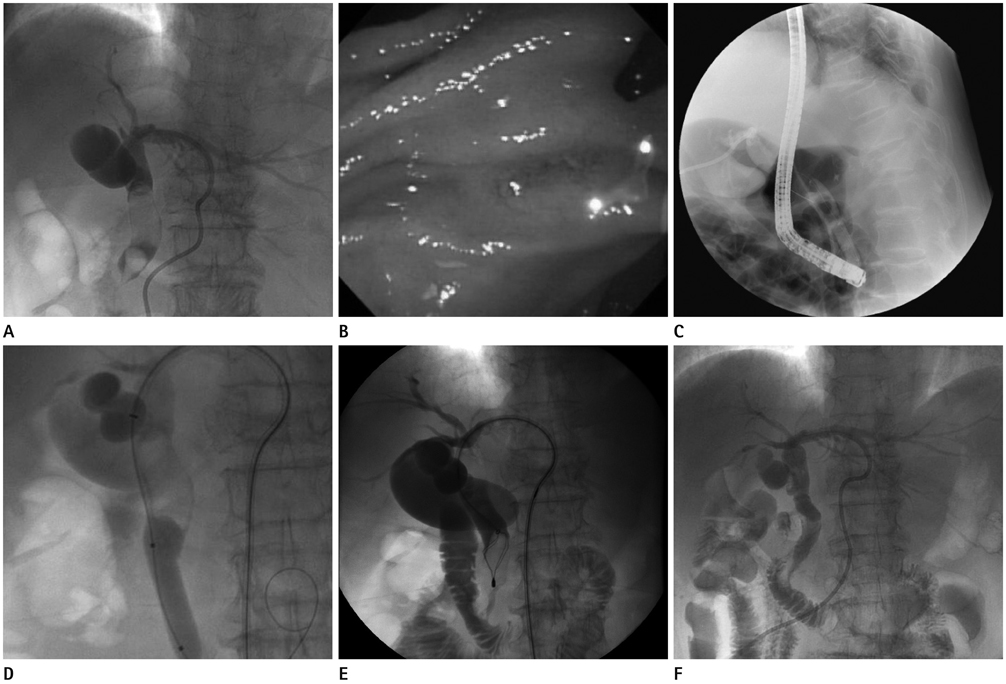

Figure